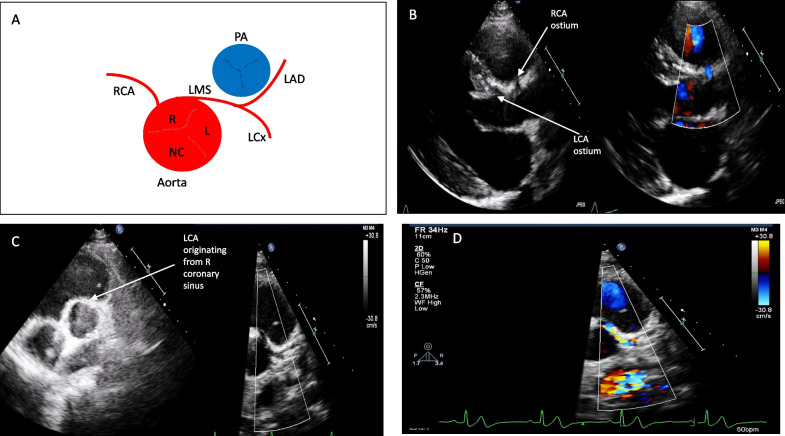

Transthoracic echocardiography is an essential and widely available diagnostic tool for assessing individuals reporting cardiovascular symptoms, monitoring those with established cardiac conditions and for preparticipation screening of athletes. While its use is well-defined in hospital and clinic settings, echocardiography is increasingly being utilised in the community, including in the rapidly expanding sub-speciality of sports cardiology. There is, however, a knowledge and practical gap in the challenging area of the assessment of coronary artery anomalies, which is an important cause of sudden cardiac death, often in asymptomatic athletic individuals. To address this, we present a step-by-step guide to facilitate the recognition and assessment of anomalous coronary arteries using transthoracic echocardiography at the bedside; whilst recognising the importance of performing dedicated cross-sectional imaging, specifically coronary computed tomography (CTCA) where clinically indicated on a case-by-case basis. This guide is intended to be useful for echocardiographers and physicians in their routine clinical practice whilst recognising that echocardiography remains a highly skill-dependent technique that relies on expertise at the bedside.